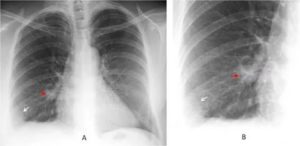

На УЗДГ вен нижних конечностей при инфаркте легкого диагностируется тромбоз глубоких вен. На рентгене легких в боковой и прямой проекциях просматриваются:

• деформация и расширение корня легкого;

• зона снижения прозрачности, имеющая вид клина;

• выпот в плевральной полости.